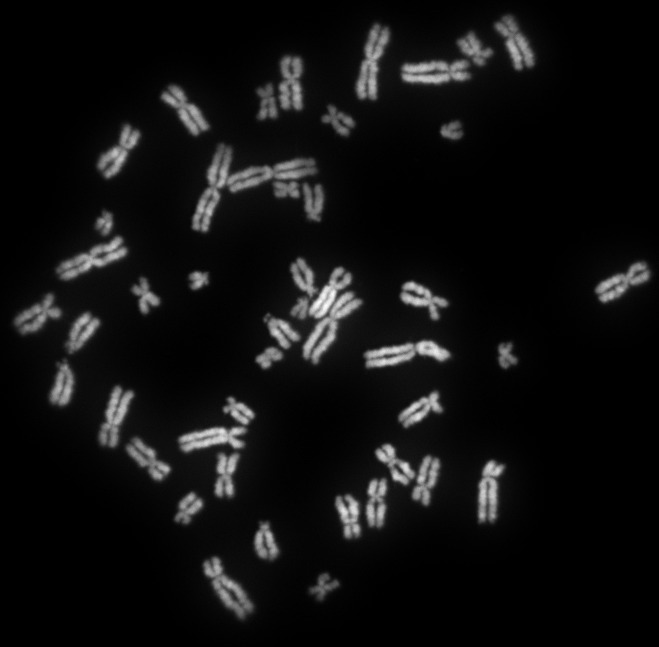

Крутовский отметил, что генетическое наследование у человека характеризуется строгим хромосомным типом. Присутствие XY влечет за собой рождение мужчины, а XX — женщины, обеспечивая стабильное соотношение один к одному в виде. Однако ученый подчеркнул, что в реальности рождается немного больше мальчиков из-за различных факторов.